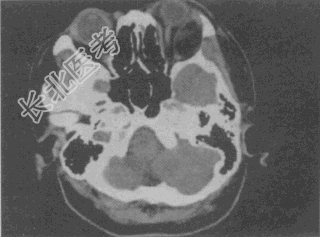

- 单项选择题女,52岁, 左眼球突出20余年,T

均正常, 影像检查如图所示,最可能的诊断是